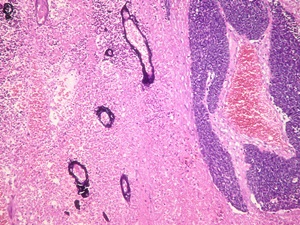

골수는 우리 몸에 필요한 적혈구, 백혈구, 혈소판과 같은 혈액세포를 만드는 조직입니다. 골수는 겉질뼈로 둘러싸인 해면뼈조직 사이의 조혈 공간을 이야기하는데요. 골수에 이상이 생기면 치명적인 문제가 발생할 수 있습니다. 골수암에 대해 궁금하신 사항은 아래를 참조하세요.

골수암은 전문용어로 급성 골수성 백혈병이라고 말합니다. 이는 정상적인 백혈구 생산을 막는 비정상적인 세포가 골수에 생성되어 축적되는 혈액 암인데요. 주로 성인에게 발생률이 높으며 나이가 많을수록 발병률이 증가하게 됩니다.